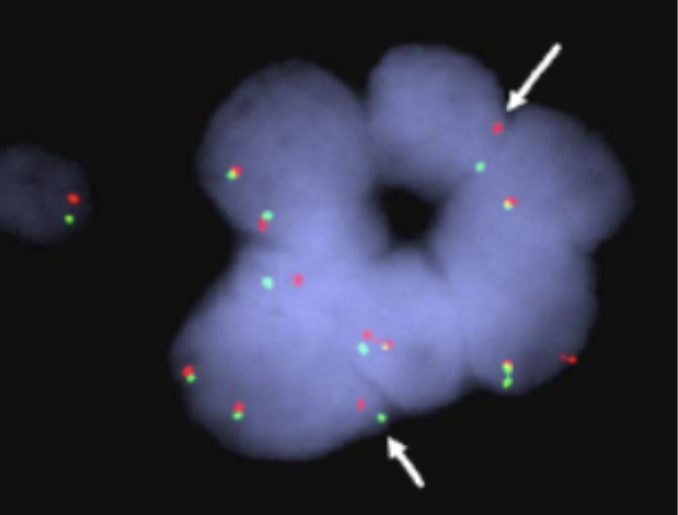

Categories of information from looking at FISH

1. Number of signals/cell

2. Location (probe diameter distance units)

3. Intensity